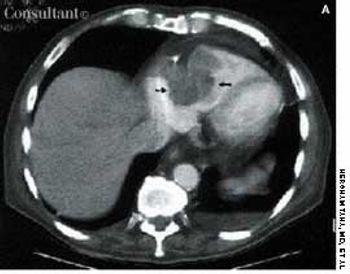

A 97-year-old woman with a history of hypertension and a paraesophageal hiatal hernia presented with abdominal distention and shortness of breath. Three days earlier, she had fallen and sustained a hairline pelvic fracture; she was evaluated in the emergency department and given narcotics for the pain. Subsequently, the patient's abdomen became increasingly distended, and she had no bowel movement for 3 days.